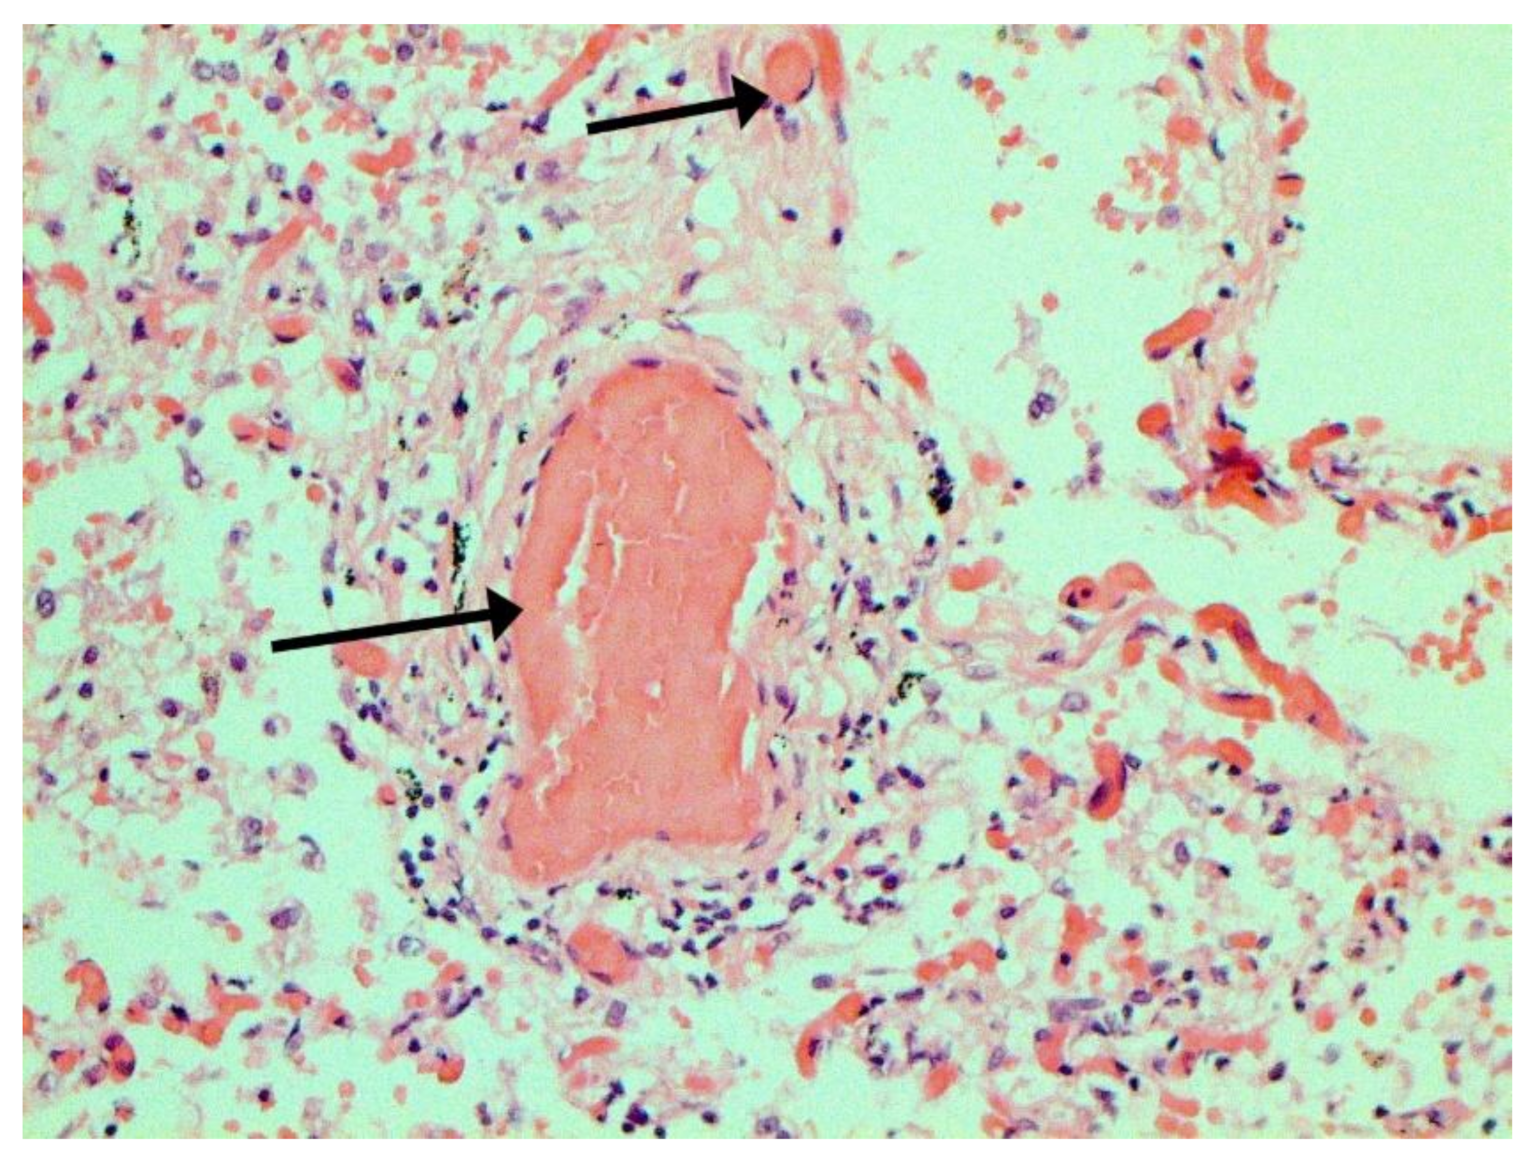

The main morphological substrate of respiratory insufficiency is diffuse alveolar damage. The term viral pneumonia, widely used in the clinic, essentially reflects its development. In turn, severe diffuse alveolar injury is synonymous with the clinical concept of “acute respiratory distress syndrome” (ARDS). In the pathogenesis of ARDS, without a doubt, the most important role is played by the damage to the microcirculatory bed, the genesis of which requires further study, but direct viral damage is most likely. COVID- 19 is characterized by a pronounced fullness of the capillaries of the interalveolar septa, as well as branches of the pulmonary arteries and veins, with erythrocyte sludge, fresh fibrin, organizing blood clots, and intrabronchial, intrabronchiolar, and intra-alveolar hemorrhages, which are a substrate for hemoptysis, as well as perivascular hemorrhages (Figure 8). Pronounced alveolar hemorrhagic syndrome is characteristic of most cases, up to the formation, in fact, of hemorrhagic infarcts (although true hemorrhagic infarcts are not uncommon). Pulmonary blood clots are important to distinguish from thromboembolism, as pulmonary embolism (PE) is also characteristic of COVID-19. Thrombosis of the pulmonary arteries sometimes progresses to the right parts of the heart, and thrombosis of the arteries of various organs with the development of their infarcts (myocardium, brain, intestines, kidneys, and spleen) is described. This distinguishes changes in the lungs in COVID-19 from those previously observed in influenza A/H1N1. Despite the pronounced hemorrhagic syndrome, significant deposits of hemosiderin are not observed.

The dynamics of changes in ARDS associated with COVID-19 can only be judged by analogy with SARS and influenza A/H1N1pdm. In the late (productive) stage (after 7–8 days or more from the onset of the disease) of diffuse alveolar damage, macroscopically the lungs are enlarged, low-air, dense, fleshy, and can resemble the density of the liver, sometimes with diffuse whitish layers and areas of different sizes. Microscopically, siderophages, a relatively (in comparison with swine influenza) small number of hyaline membranes (Figure 9), fibrin, squamous metaplasia of the bronchial, and bronchiolar and alveolar epithelium can be detected in the lumens of the alveoli, respiratory and terminal bronchioles, the thickening of the interalveolar septa due to sclerosis, lymphoid (mostly CD3+ and CD 8+) (Figure 10 and Figure 11) and macrophage (Figure 12) infiltration, and the proliferation of type II alveolocytes. The nature of cytoproliferative changes of the epithelium in the trachea and bronchi remains unclear. In the final stage of the disease, sections of fibrous tissue may develop in all parts of the lungs (usually in the lower lobes) (Figure 13), which contributes to the development of chronic respiratory failure. It is notable that near the overgrowth of collagen fibers in the lungs, neoangiogenesis is also typical (Figure 14). The electron microscopic study revealed changed viral particles (Figure 15).

In many vessels, we also observe thrombi in different vessels (Figure 16 and Figure 17). We succeeded in detecting virus spike antigen in endothelial cells as well as in other layers of vascular walls. The formation of fibrin thrombi in blood vessels (probably DIC) and infiltration by T lymphocytes, including cytotoxic cells (Figure 18 and Figure 19), were seen not only in the parenchyma of the organs but in the surrounding tissues as well. It is important to compare the localization of virus antigens and cytotoxic CD8+ cells (Figure 20).

Figure 9. Hyaline membranes (arrows) in lung. H-E ×100.